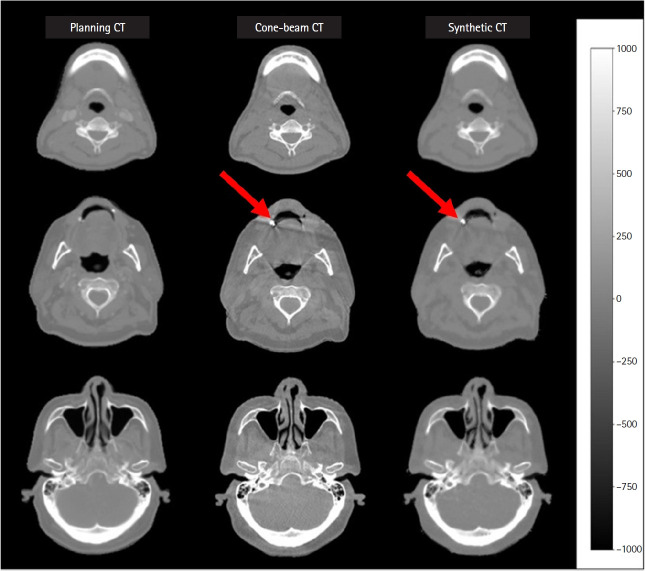

Results: MAE, RMSE, PSNR, and SSIM showed improvements from their initial values of 53.15 ± 40.09, 153.99 ± 79.78, 47.91 ± 4.98 dB, and 0.97 ± 0.02 to 41.47 ± 30.59, 130.39 ± 78.06, 49.93 ± 6.00 dB, and 0.98 ± 0.02, respectively. Regarding dose evaluation, 3D gamma passing rates for dose distribution within sCT images under 2%/2 mm, 3%/2 mm, and 3%/3 mm criteria, yielded passing rates of 92.1% ± 3.8%, 93.8% ± 3.0%, and 96.9% ± 2.0%, respectively. The sCT images exhibited minor variations in the percentage dose distribution of the investigated target and structure volumes. However, it is worth noting that the sCT images exhibited anatomical variations when compared to the pCT images.

Conclusion: These findings highlight the potential of the supervised U-Net deep learningmodel in generating kV-CBCT-based sCT images for ART in patients with HNC.